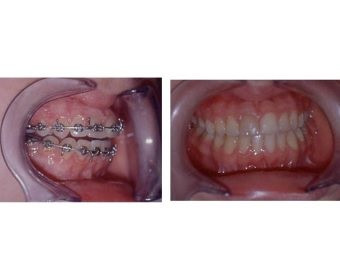

Casos y procedimientos

Envíado por Dr. Francisco Iván Ordóñez Carranza